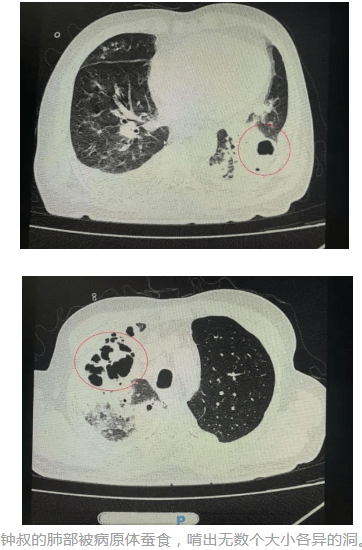

一个肺脓肿患者,差点被误诊为肺癌 这个病人50岁,咳嗽,咳痰四五天了